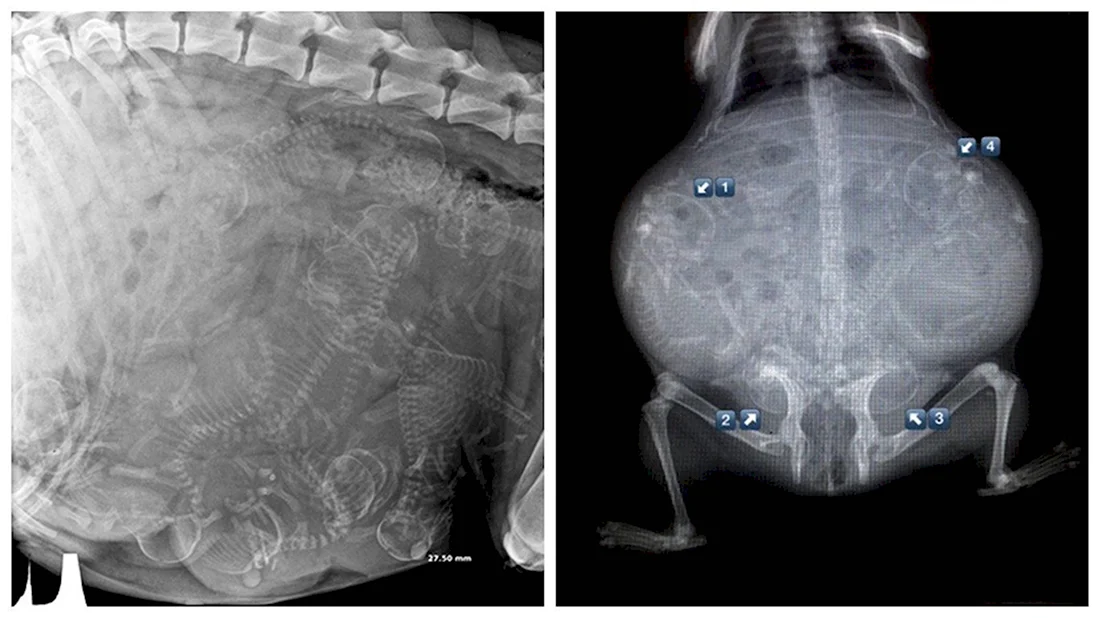

Погрузитесь в волшебный мир развития эмбриона кошки с помощью этой захватывающей галереи фотографий! Вас ждут 39 потрясающих фото и картинок, которые позволят вам увидеть каждый этап развития эмбриона. Эта подборка фотографий сразу привлечет ваше внимание и заставит задуматься о том, насколько удивительным может быть природа. Порадуйте свои глаза этой удивительной коллекцией фотографий и узнайте больше об удивительной жизни эмбрионов кошек!